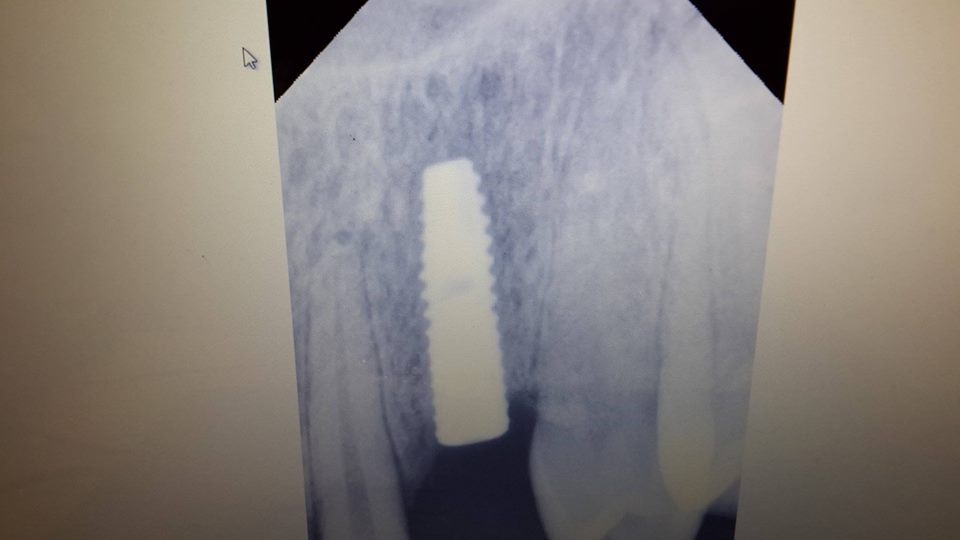

Canine restoration using implantation

To successfully restore the canine, the patient was simultaneously removed a tooth and used bone material.